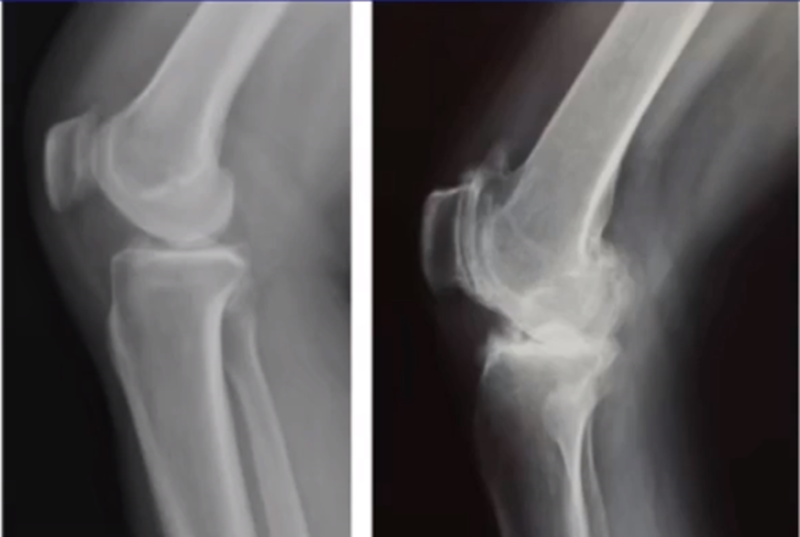

标准侧位片,内外髁完全重叠,胫骨平台也一样,如果检查不标准,X线片结果会影响判断。

侧位片可以显示胫骨平台磨损部位,在判断前交叉韧带功能是否完好方面有重要意义。当磨损部位在前方或中前方,没有延伸到胫骨平台后缘时,说明前交叉韧带功能正常;当磨损部位延伸到胫骨平台后方,甚至引起后方半脱位状态时,说明前交叉韧带功能缺失或损害,此时不适合做单髁。

AMOA的侧位X线表现

ACL功能完好是单髁重要的适应证。当ACL失去功能,导致后方软骨磨损或者骨缺损,此时为整个内侧或全间室的骨关节炎,不是单髁的适应证了。